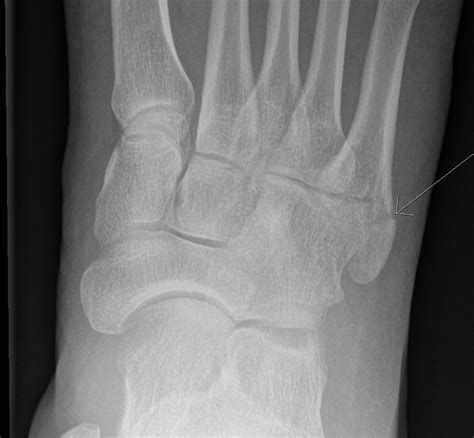

• X-Rays: X-rays are the primary imaging tool used to confirm the presence and location of the fracture.

• pictures of 5th metatarsal fracture